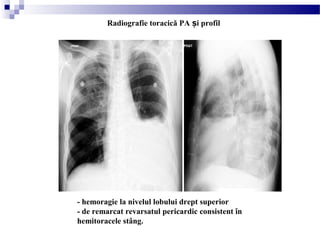

- hemoragie la nivelul lobului drept superior

- de remarcat revarsatul pericardic consistent în

hemitoracele stâng.

Radiografie toracică PA i profilș